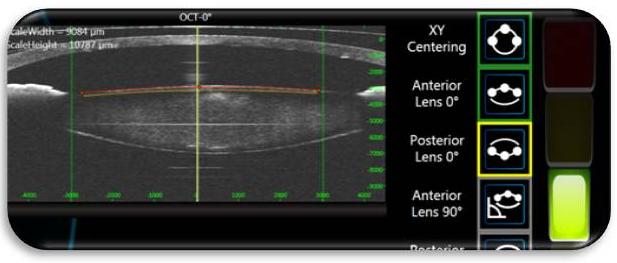

- 收妥治療費用後,視光師會再替你量度角膜弧度